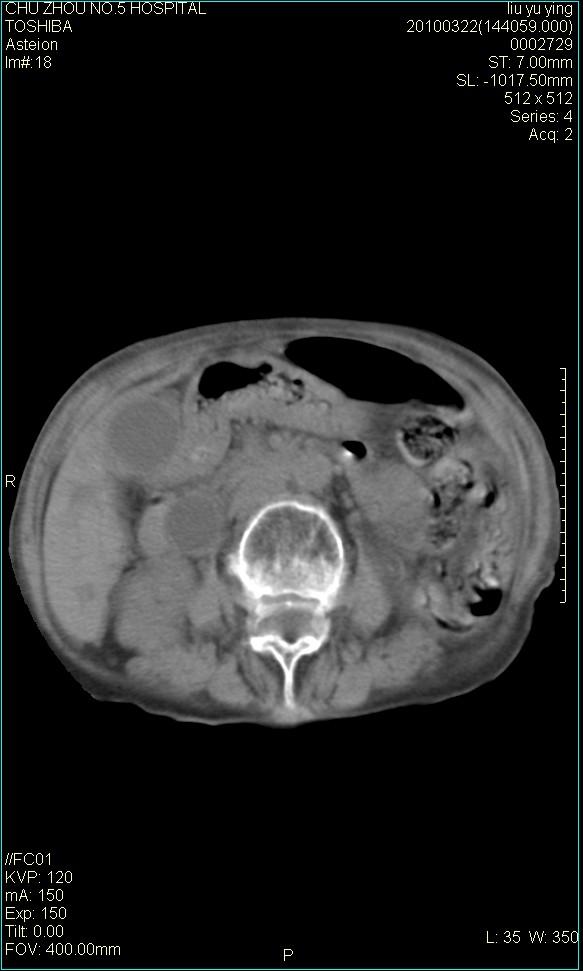

以下是引用科室第一人在2010-3-23 6:50:00的发言:[br]胆总管下段梗阻,多为肿瘤性病变,巨形胆囊,胆囊炎胆囊窝积液。[br]双侧胸腔积液,右降

以下是引用随光逐影在2010-3-23 8:12:00的发言:[br]1)胆系低位梗阻(肝内外胆管扩张,胆囊增大),原因待查。2)胆囊炎。3)双侧少量胸腔积液。4)降主动脉迂曲。